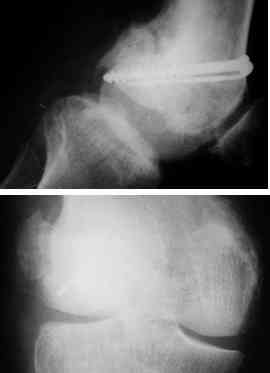

Notes at that time mention a compound fracture dislocation, with a loss of part of the lateral condyle. This was treated by debridement, and external fixation. After two weeks, the lateral condyle (coronal fracture) was fixed by a screw and k wire in an AP direction.

At present, he has a valgus deformity of the knee, with 0-45 degrees of movt. The knee is stable to examination, could not be corrected to neutral from the existing valgus, and despite the deformity he is walking on it, albeit with pain and some difficulty.

He was referred to me for correction of his deformity.